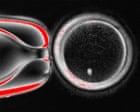

Researchers have created human eggs from skin cells, potentially transforming IVF treatment for couples who have no other options.

The work is at an early stage but if scientists can perfect the process it would provide genetically related eggs for women who are infertile because of older age, illness or medical treatment. The same procedure could be used to make eggs for same-sex male couples.